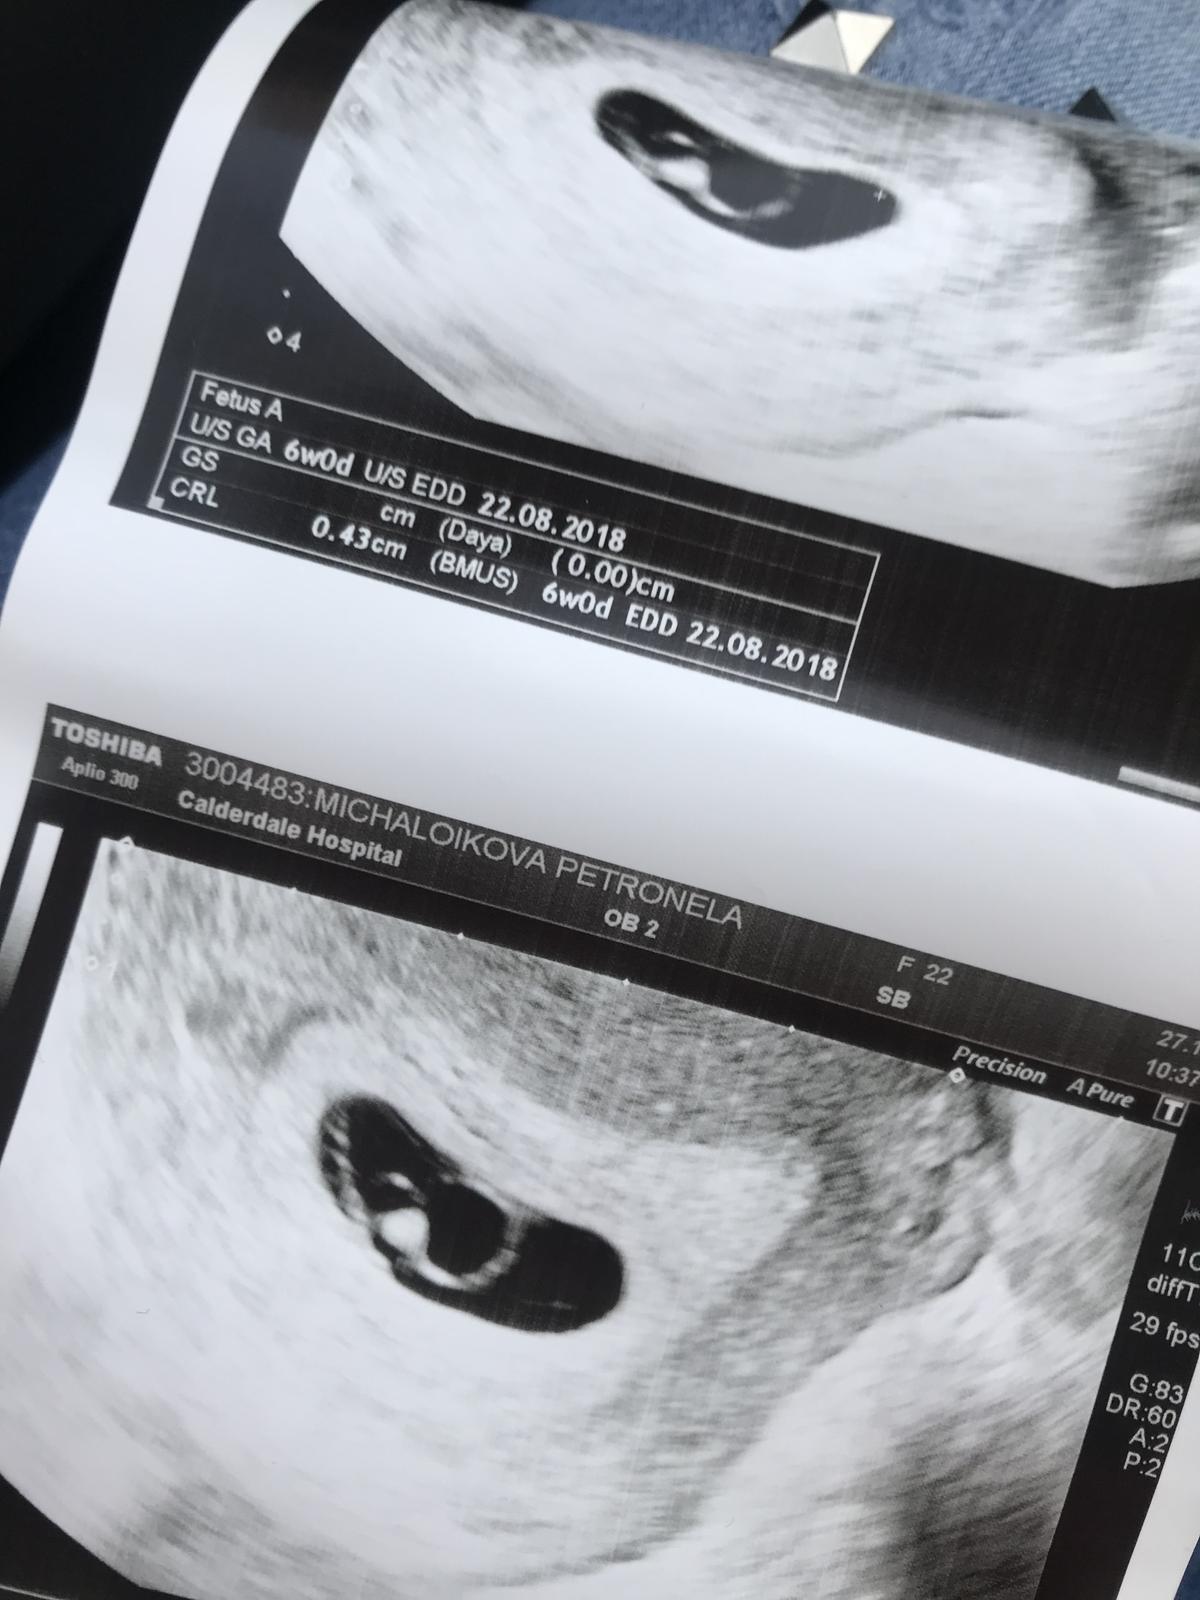

Takze baby bola som na gyn ❤️ Bábätko je kde ma byt a už nám bije aj srdiečko ❤️Som strašne šťastná ❤️

Zdravim...dnes som bola na ultrazvuku ( prikladam fotku ) som v 7tt

@nellynnnka gratulujem. Inak mne každý podľa fotky hovoril, že čakám dve...ale skutočne len jedno a aj jedno srdiečko bilo ❤️